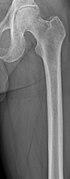

Medical imaging

The diagnostic examination of a person with suspected multiple myeloma typically includes a skeletal survey. This is a series of X-rays of the skull, axial skeleton, and proximal long bones. Myeloma activity sometimes appears as "lytic lesions" (with local disappearance of normal bone due to resorption). And on the skull X-ray as "punched-out lesions" (pepper-pot skull). Lesions may also be sclerotic, which is seen as radiodense.[52] Overall, the radiodensity of myeloma is between −30 and 120 Hounsfield units (HU).[53] Magnetic resonance imaging is more sensitive than simple X-rays in the detection of lytic lesions, and may supersede a skeletal survey, especially when vertebral disease is suspected. Occasionally, a CT scan is performed to measure the size of soft-tissue plasmacytomas. Bone scans are typically not of any additional value in the workup of people with myeloma (no new bone formation; lytic lesions not well visualized on bone scan).